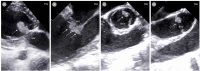

Belonging to the normal oral, gastrointestinal, and urogenital flora, Abiotrophia defectiva is responsible for 1-2 % of all infective endocarditis (IE) cases. The manifestation of A.defectiva endocarditis may by atypical, without fever. Difficult to isolate pathogen requires special culture media. A 45-year-old female was admitted due to anemia and progressive weight loss (8 kg in 6 months). She had a history of benign mitral valve (MV) prolapse and non-stenotic bicuspid aortic valve (BAV). In echocardiography, large vegetations on MV and small vegetation on BAV were found. An enriched medium for fastidious pathogens was used. A. defectiva was identified using biochemical analysis with VITEK-2 Compact. In the fourth week of antibiotic therapy, she required urgent MV replacement due to MV regurgitation progression while vegetation on BAV disappeared. Although patient's frailty and underweight caused prolonged postoperative wound healing, she was transferred to rehabilitation in good conditions. No relapse of IE was observed during five-month follow-up.